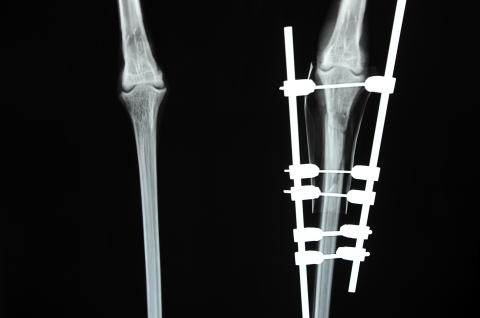

骨は4つに割れて

身体検査で疑ったとおり、左足の中足骨が関節付近で4つに割れていました。列車と衝突した事を考えると、肝臓や腎臓などを大きく損傷していても不思議では無いのですが、検査の結果、体腔内に大量出血等は確認されませんでした。

全身麻酔下で緊急手術

関節付近における複合骨折の治療には経験が必要とされます。身体への負担を考えると、長時間全身麻酔をかけることもできません。齊藤獣医師の執刀により、ガス麻酔下で特殊なピンを用いた整復術を実施しました。約30分で手術は無事終了し、足は元の形に戻りました。

骨片は元の位置に

レントゲン写真でハシゴのように見えるのは、骨を繋ぐための特殊なピン等です。鳥の骨は竹のように中空で、最小限のピンを用いて細かく割れた骨がいずれも動かないように止めるためには、ピンを打つ位置と角度がとても重要になります。